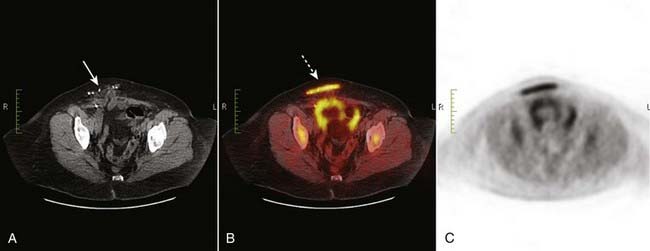

image False-positive findings may occur with inflammatory processes, in benign neoplasms, and in hyperplastic but benign tissue, all of which are FDG avid (Fig. 28).

image

Figure 28 FGG avid scar from hernia repair.

PET scans are most often used to diagnose or confirm malignancy. False-positive findings may occur with inflammatory processes, in benign neoplasms, and in hyperplastic but benign tissue, all of which are FDG avid. (A) This patient had previously undergone a hernia repair on the right side (solid white arrow). The PET/CT fusion image (B) shows intense uptake in the inflammatory reaction surrounding the site of the repair (dotted white arrow).